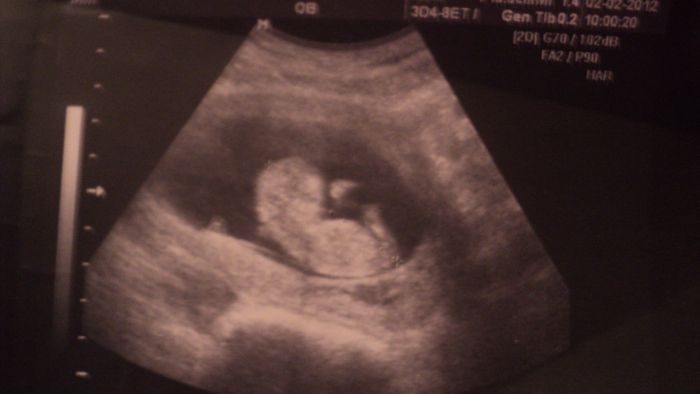

Konečně vám tady posílám fotečku bříška a prcka, tak se mrkněte

Ahoj holky, vy jste se zase rozepsaly. Vztahy jsou zapeklitá věc, já jsem na chlapy taky neměla moc štěstí, ale ted si stěžovat nemůžu. Vlastně mám co jsem chtěla. Jak se říká jednou jsi nahoře a jednou dole. Ale jelikož se s přítelem vídáme jen o víkendu, tak to jde. Sice nemám jistotu, jak to půjde dál, přítel původně děti vůbec nechtěl, ale chybička se vloudila. Ve středu jsme byly v Brně na screeningu, tak byl z ultrazvuku úplně hotový. Nechtěl věřit tomu, jak je mrňous tak hrozně moc živý, celou dobu sebou pěkně mrskal.